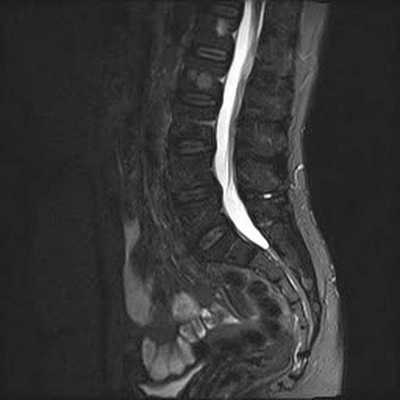

МРТ позвоночника. Сагиттальная Т2-взвешенная МРТ, срединный срез поясничного отдела. Показана нумерация позвонков, измерения позвоночного канала (черная линия). Т- дуральный мешок с ярким ликвором. L- желтая связка. Sacrum - крестец. D - межпозвоночный диск. Голубым выделен остистый отросток, желтым - тело позвонка, Голубые точки - ход корешков.

МРТ позвоночника. Парасагиттальная (околосрединная) Т2-взвешенная МРТ поясничного отдела. Красными стрелками показаны корешки.